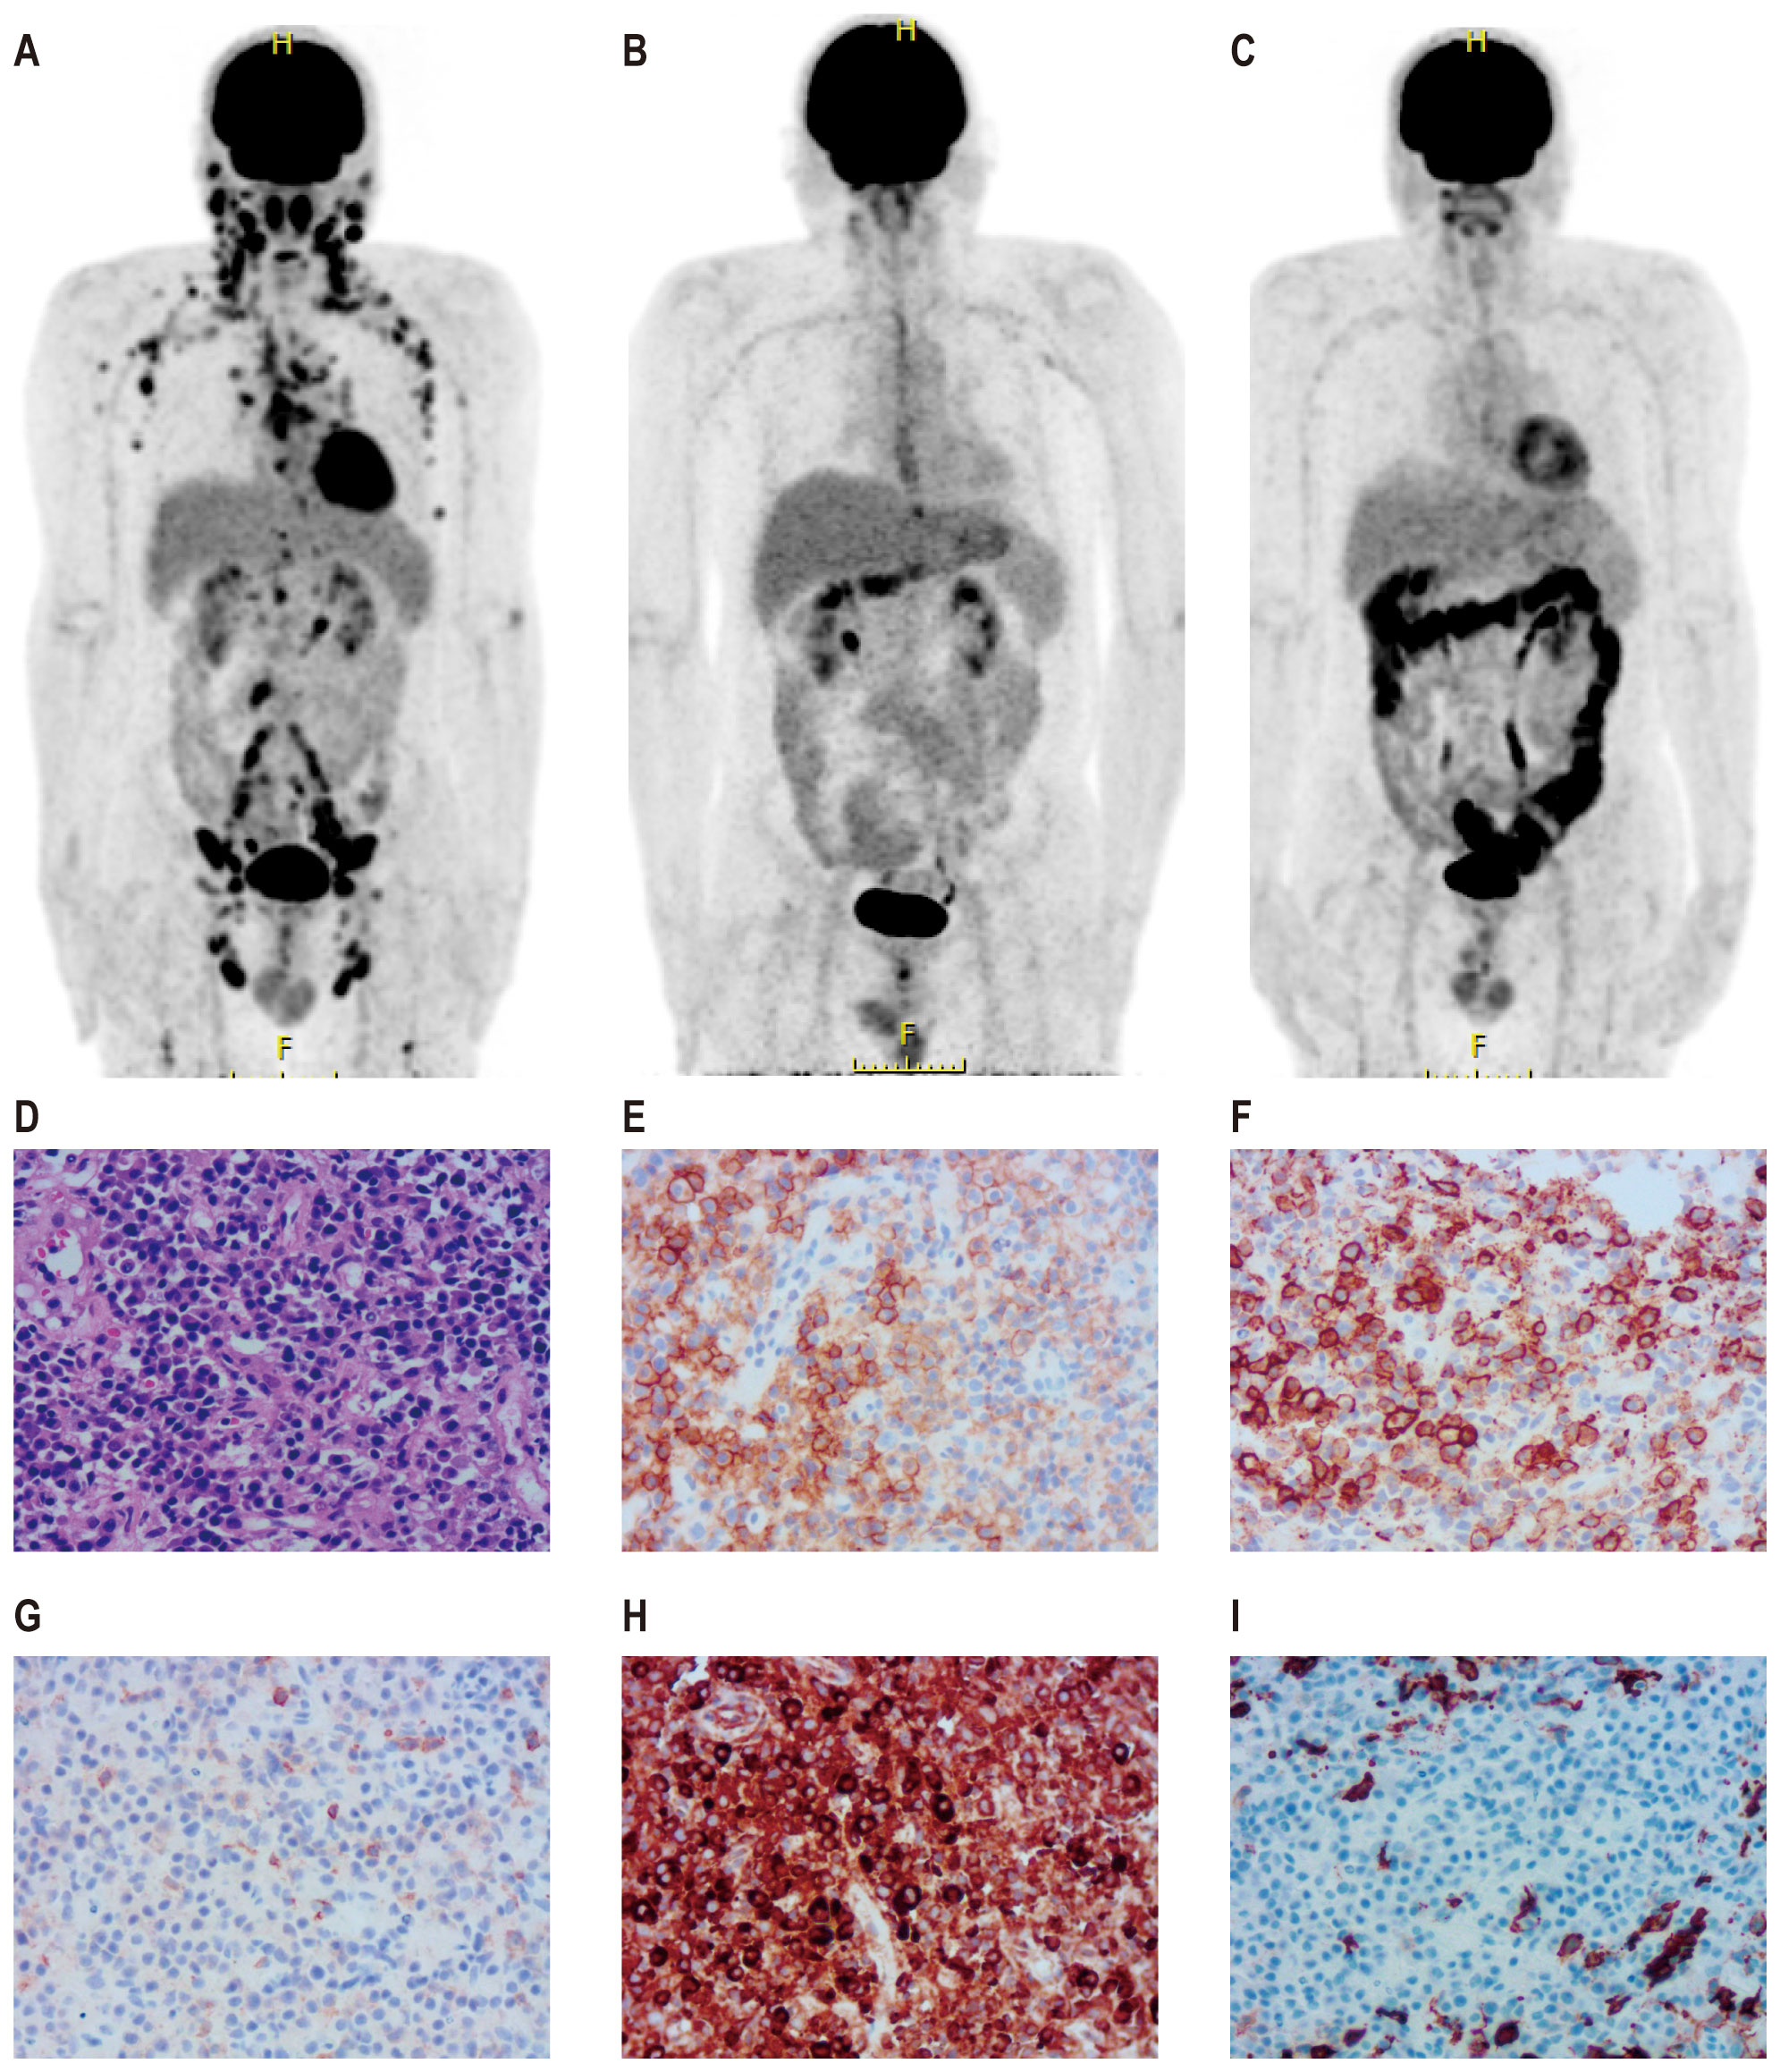

CT scan images labeled A to F show different abdominal cross-sections. Images A, B, and C have red arrows pointing to specific areas of interest within the abdominal cavity. Images D, E, and F show similar cross-sections without arrows.

Figure 2. CT images before and after CAR-T therapy. CT scans following two cycles of daratumumab in combination with GemOx showed no treatment response (A–C). One month after the transfusion of CD19 and CD22 CAR-T cells, the patient achieved a complete response (D–F).

The patient received second-line treatment: daratumumab combined with GemOx for two cycles (daretuzumab 800 mg qw; gemcitabine 1 g/m2 d1, oxaliplatin 100 mg/m2 d1, q2w). CT scans revealed disease progression after two cycles of second-line treatment (Figures 2A–C). The largest lymph nodes were in the pelvic cavity, with a cross-section of 4.8 cm × 2.4 cm. A biopsy of the right pelvic mass was performed. The pathological results indicated the presence of PBL. Tumor cells were positive for CD38, CD138, CD22, CD79a, MUM1, CD45, and kappa; partial positive for CD19 and EBER; negative for CD2, CD3, CD5, CD10, CD20, CD56, cyclin D1, ALKp80, HHV-8, MPO, lambda and IgG; and 5% positive for CD30; the Ki-67 positivity rate was 70% (Figures 1D–I). Immunostaining revealed CD19 expression in 15% of tumor cells and CD22 expression in nearly all cells (95%). As CD19 and CD22 are targets of CAR-T cell therapy, CAR-T therapy was considered as third-line treatment.

Peripheral blood was collected for the generation of two distinct CAR-T cell products targeting CD19 and CD22, respectively. The CD19-directed CAR-T cells feature an anti-CD19 single-chain variable fragment (scFv), fused to a CD8α hinge and transmembrane domain, a 4-1BB (CD137) costimulatory domain, and a CD3ζ intracellular signaling domain. The CD22-specific CAR-T construct followed a similar design, with the anti-CD19 scFv substituted by an anti-CD22 scFv. The patient received cyclophosphamide and fludarabine for lymphodepletion. CD19 CAR-T cells (2.9 × 106/kg) followed by CD22 CAR-T cells (3.7 × 106/kg) were transfused sequentially to the patient with an interval of six days. White blood cells and neutrophilic granulocytes decreased after chemotherapy, but without neutropenia (Figure 3A). The patient showed no cytokine release syndrome response after CAR-T therapy. Ferritin slightly increased on day 4 following CD19 CAR-T transfusion (Figure 3A). CAR-T cells increased following transfusion and were detectable three months after transfusion (Figure 3B). One month after CAR-T transfusion, CT scan showed no enlarged lymph nodes (Figures 2D–F). Three months later, PET-CT showed a complete metabolic response (Figure 1C). Since the CAR-T transfusion, the duration of complete remission was more than 12 months until this submission.